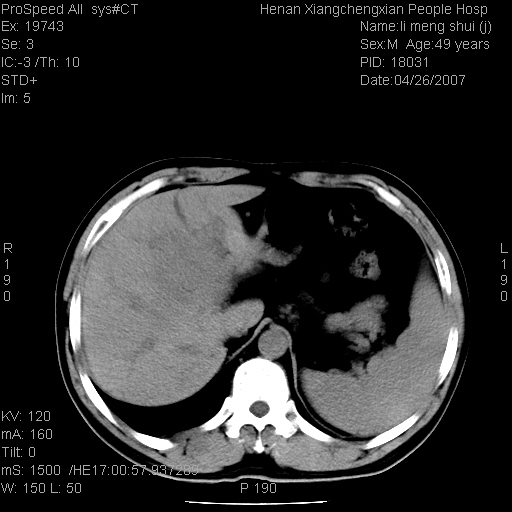

| 患者,男,49岁, 腹疼伴恶心\\呕吐20天,20天前无明显诱因出现右上腹部疼痛,钝疼,无放射,伴恶心\\呕吐,不伴发热.患者不愿增强. b超:肝脏右叶实性占位. ct:肝脏右叶可见一巨块状圆形低密度影,大小约93mm*84mm,其内可见点状高密度影,胆囊、胰腺、脾脏大小、形态及密度未见异常,腹膜后间隙未见肿大淋巴结影。 印象:肝脏右叶巨大肿块,性质待定,建议增强并穿刺活检进一步确诊。 ct平扫: ![]() ![]() ![]() ![]() ![]() ![]() ![]() ![]() ![]() ![]() ![]() ![]() ![]() ![]() ![]() ![]() ![]() 肝脏右叶肿块ct引导下穿刺活检术 患者于16时05分仰卧于ct检查台上,首先行肝脏ct扫描确定进针位置、深度、角度。在局麻下行ct引导下肝脏右叶肿块穿刺活检术。常规消毒、铺巾、局麻。在ct引导下使活检针经右侧腋中线、第9肋间隙垂直胸壁进针90mm,针头进入病变预定位置。在病变预定位置多点、多方向抽取小米样病变组织多块,涂片五张送病理检查。术后穿刺点局部无出血,未出现腹腔积液等并发症。术中及术后患者生命体征稳定,手术于17时10分成功完成。患者安返病房。 穿刺片 ![]() ![]() ![]() ![]() ![]() ![]() ![]() ![]() ![]() ![]() ![]() ![]() ![]() ![]() ![]() ![]() 病理结果肝细胞癌 ![]() 原贴地址:http://www.radinet.com.cn/forum_view.asp?forum_id=4&view_id=24130 ok |